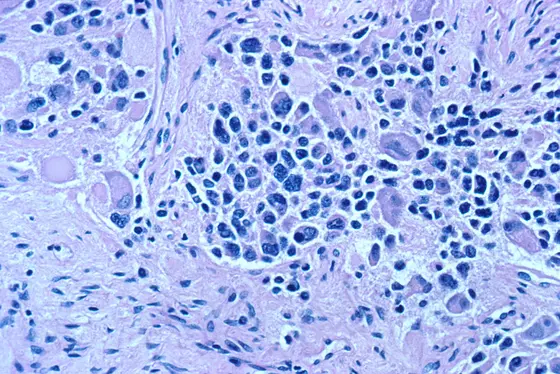

Neuroblastoma, a malignant type of tumor that occurs primarily in babies and infants, arises from cells of the embryonic nervous system. The disease can take extremely varying clinical courses, ranging from spontaneous regression to fatal outcome even after intensive treatment.

Compared to the unspecific HDAC inhibitor, the selective agent was equally or even more capable of slowing down neuroblastoma growth. Tumor cells that had been treated with the HDAC8 inhibitor developed characteristics of mature neurons. Their growth rate slowed down and increasing quantities of them died from programmed cell death – a capability that has been lost in many cancer cells.